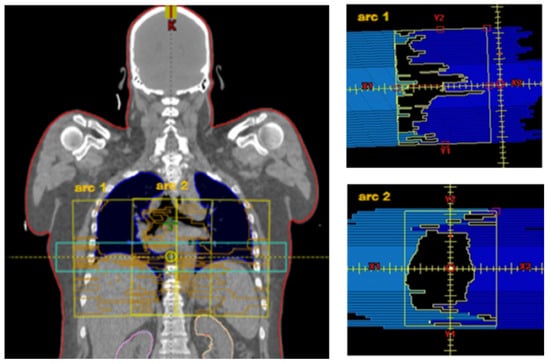

2.2. Treatment Planning